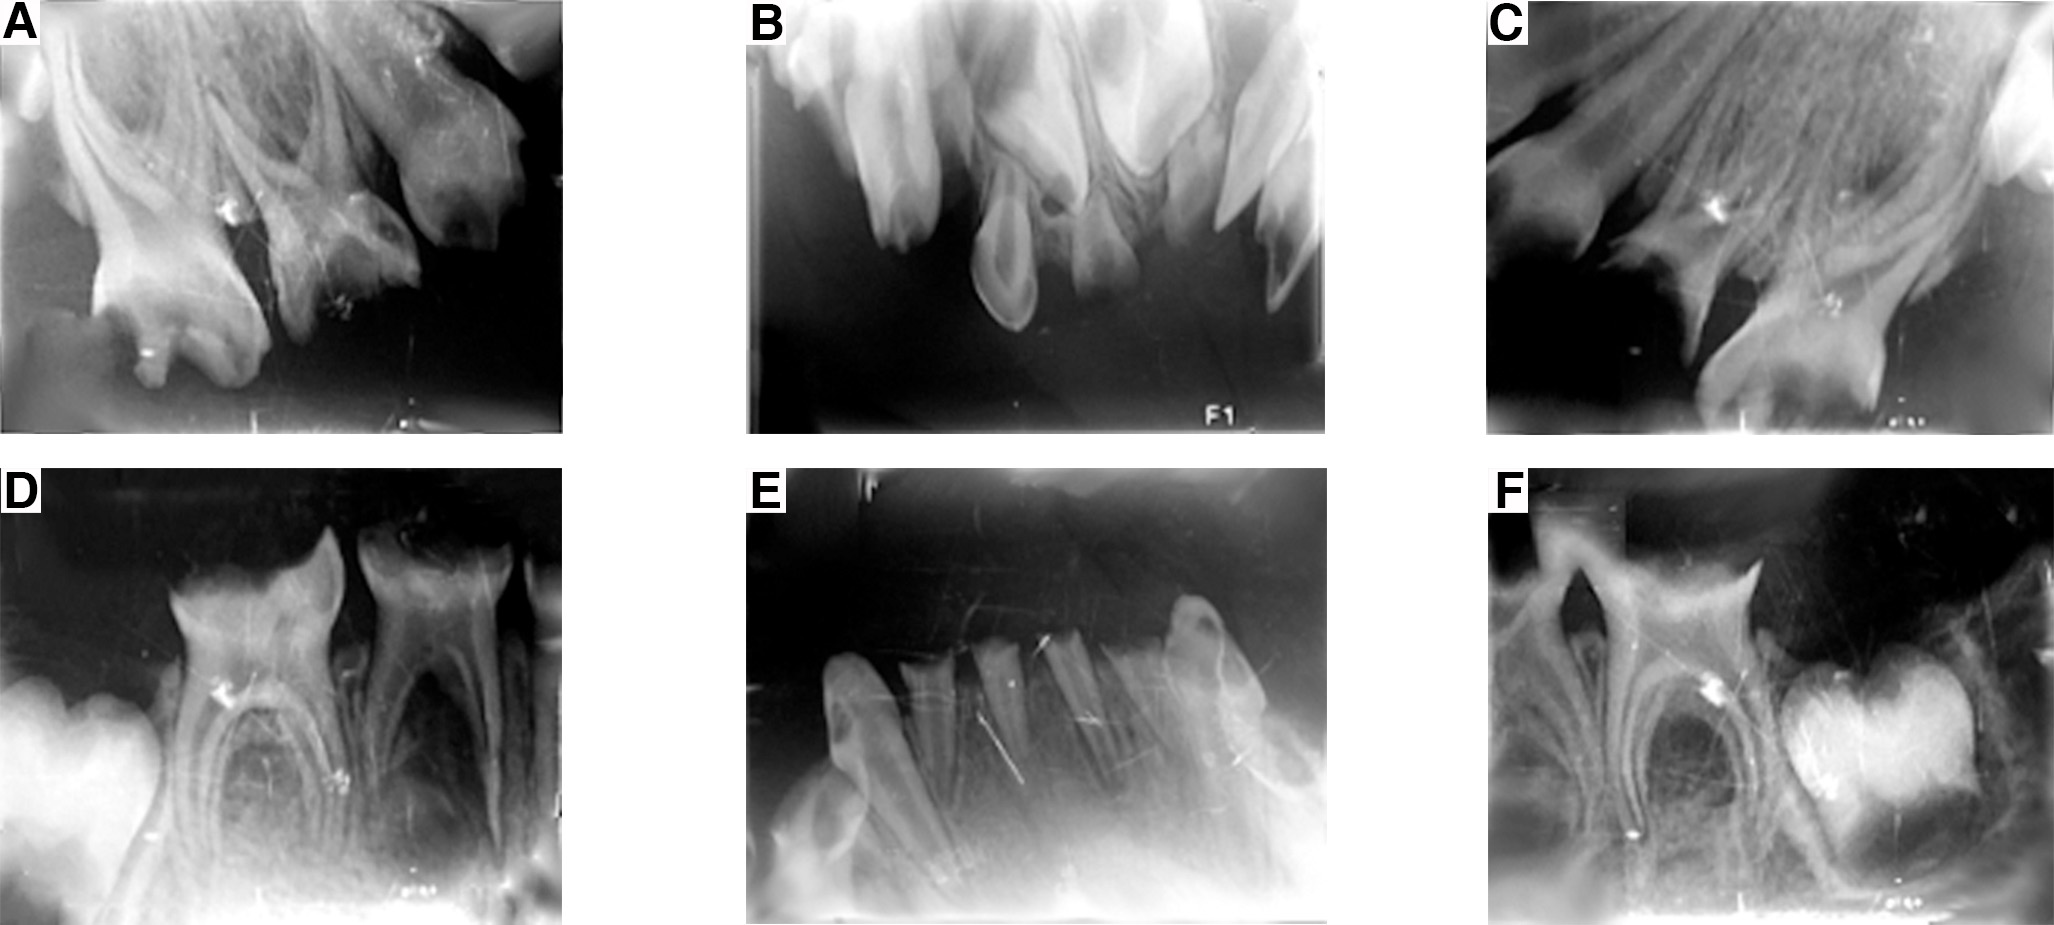

El tratamiento odontológico inicial consistió en la toma de radiografías periapicales de los cuatro cuadrantes, al igual que dos radiografías oclusales oblicuas, superior e inferior, respectivamente (figura 3 A, B, C, D, E y F), y una radiografía panorámica (figura 4). Se realizó interconsulta con el pediatra de cabecera explicando el diagnóstico obtenido de la revisión clínica y radiográfica, con el fin de conseguir la autorización para el procedimiento bajo anestesia general.

Figura 3. Radiografías iniciales periapicales y oclusales superiores e inferiores.